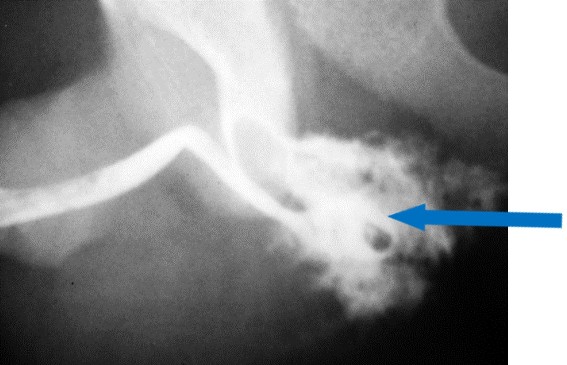

-Πλήρης ρήξη της οπίσθιας ουρήθρας

Σωστά. Κατά την ανιούσα ουρηθρογραφία υπάρχει έξοδος σκιαγραφικού στην περιοχή της μεμβρανώδους ουρήθρας και αδυναμία άφιξης του σκιαγραφικού στην ουροδόχο κύστη (ιδέ εικόνα)

Έξοδος σκιαγραφικού από τηυν οπίσθια ουρήθρα (μπλέ βέλος)